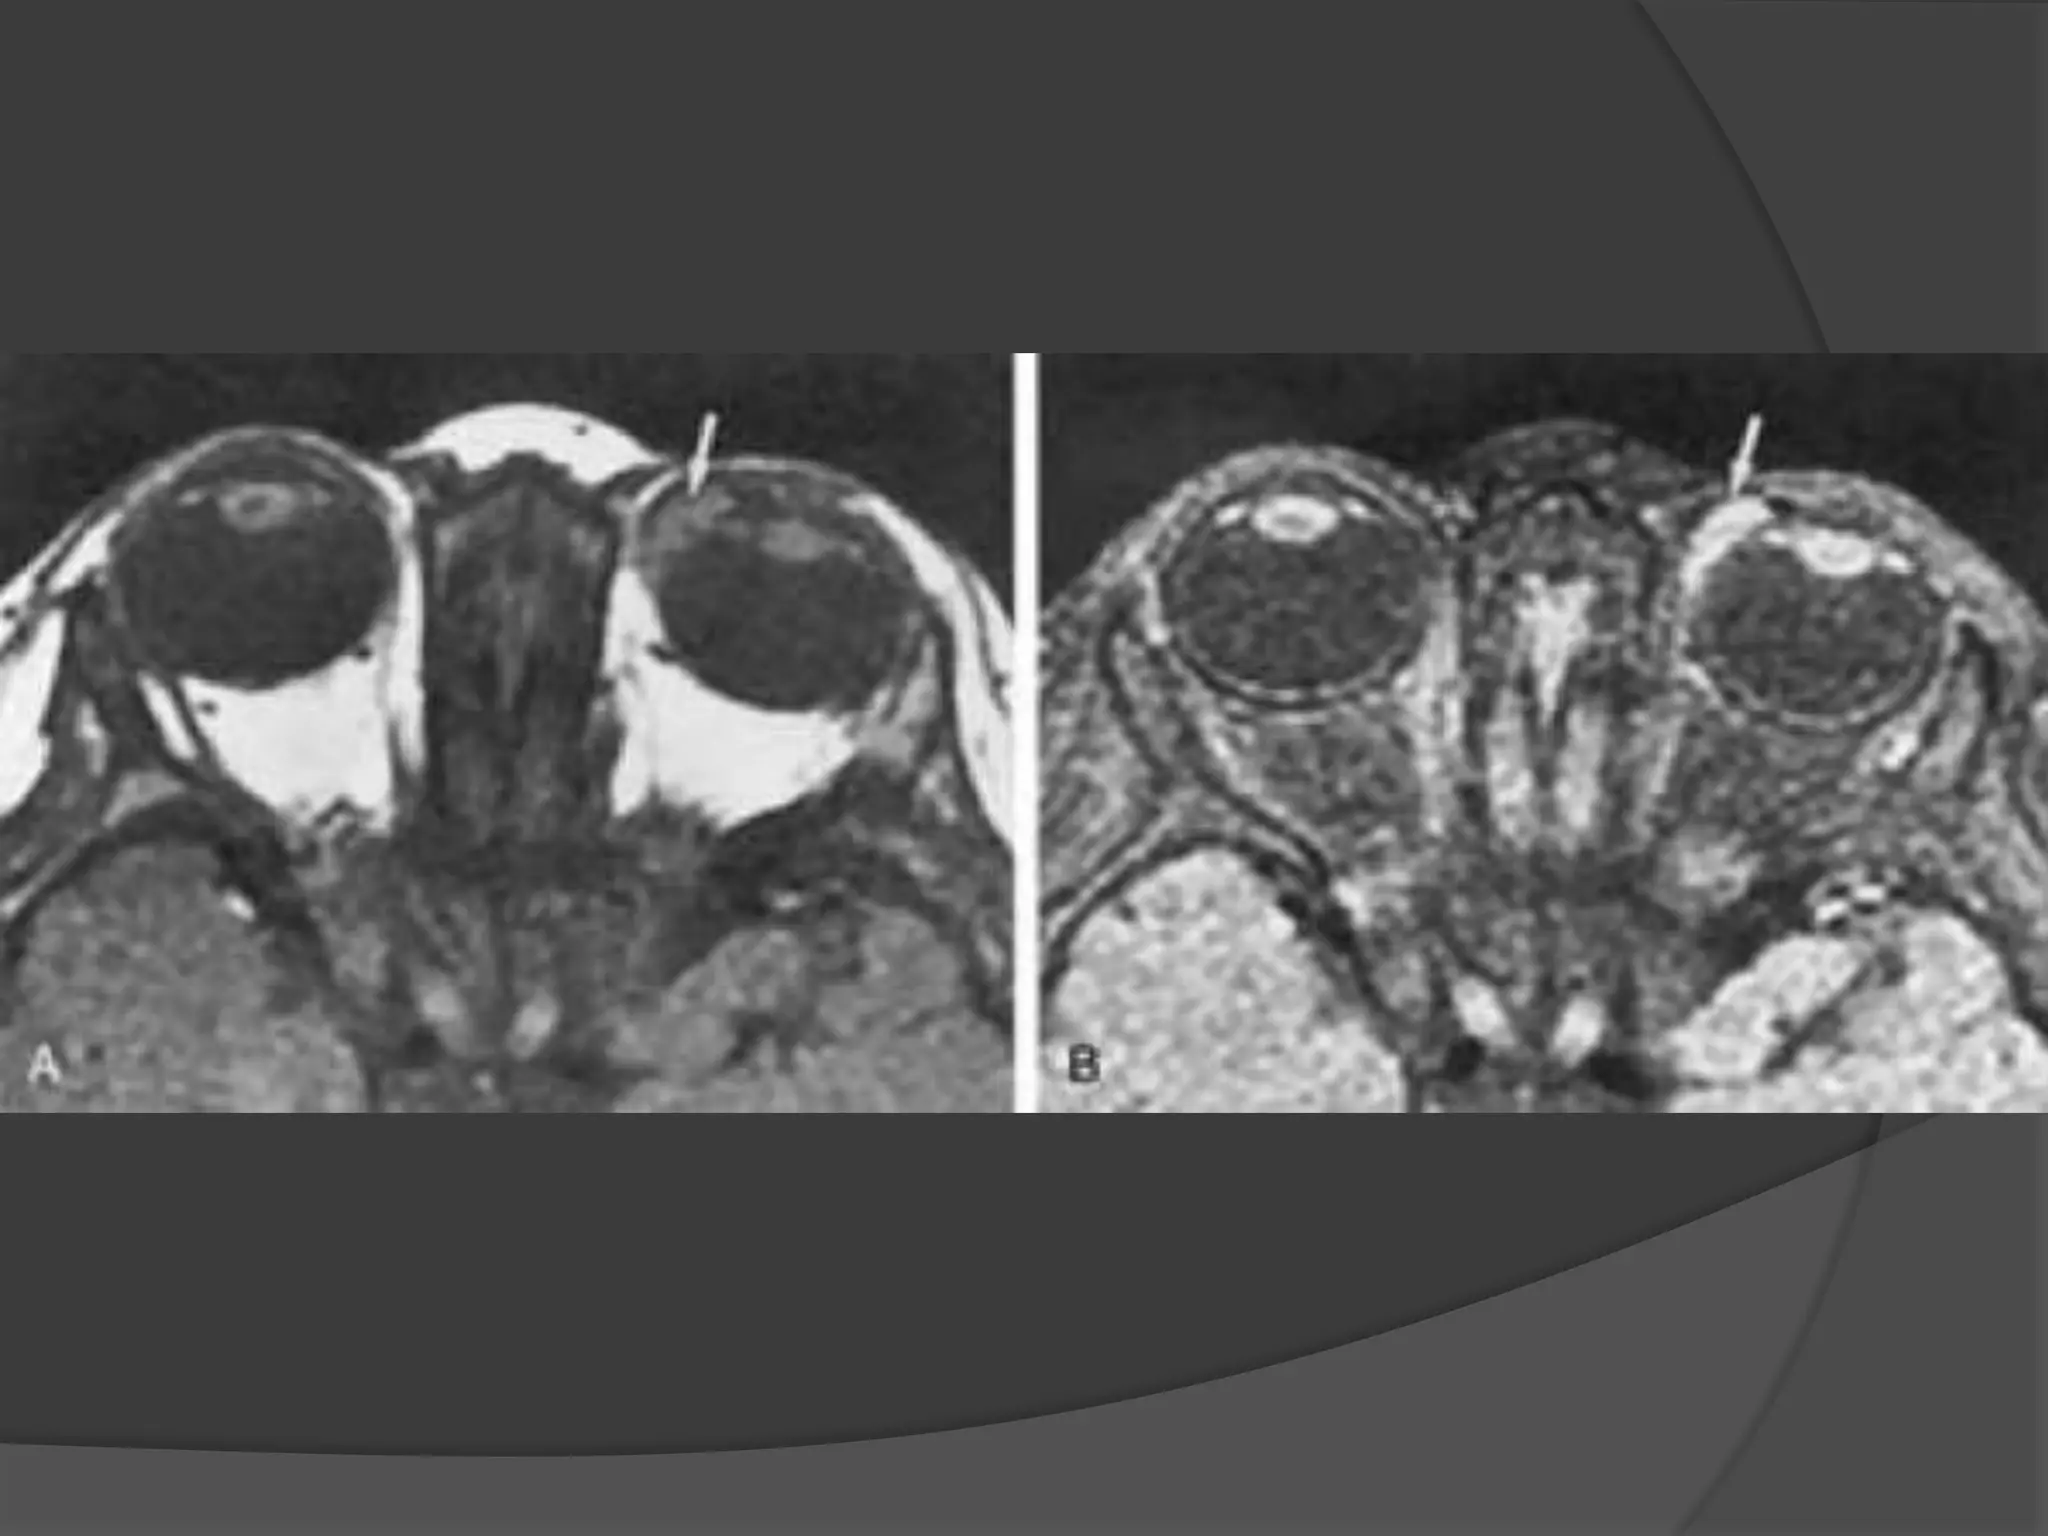

Optic Neuritis. CE Fat Sat T1W axial

(B) MR images demonstrate subtle enlargement and enhancement of the left

optic nerve (curved arrow).

T 2 WI (C) demonstrates corresponding increased signal intensity (straight

arrow).

Optic Neuritis. CEFat Sat T1W axial (B) MR images demonstrate subtle enlargement and enhancement of the left optic nerve (curved arrow). T 2 WI (C) demonstrates corresponding increased signal intensity (straight arrow).